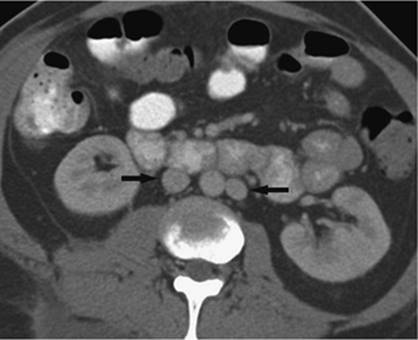

Whereas percutaneous biliary interventions gained popularity in the 1970s and 1980s, the development of endoscopic retrograde cholangiopancreatography (ERCP) has largely replaced the percutaneous approach for many disease states. However, the technique of choice will mainly depend on the skills available by physicians at the local institution (28). Additionally, there are instances where a percutaneous approach is preferred over an ERCP, mainly instances where ERCP fails, or ERCP is not an option due to prior intestinal surgery that does not allow the endoscope to reach the biliary tree (Figs. 35.14 and 35.15).

000431

Figure 35.14. Failed endoscopic placement of common bile duct (CBD) stent due to the presence of a large mass (black arrow) within the CBD. (Image courtesy of James Caridi, MD.)

000434

Figure 35.15. Successful percutaneous drainage using a left-sided biliary duct. Note that the drainage catheter has been advanced past the obstruction and into the small intestine. (Image courtesy of James Caridi, MD.)

Figure 35.16. Patient presents with biliary obstruction. On hospital day 1, external drainage has been achieved using a right-sided bile duct approach. Cholangiogram shows complete obstruction in the mid common bile duct (CBD) (black arrow).

The indications for percutaneous biliary drainage include palliation of an unresectable primary or secondary malignancy of the liver causing biliary obstruction, benign strictures including biliary-enteric anastomosis as seen in liver transplant patients, sepsis secondary to biliary obstruction, preoperative decompression, stone removal, bile leak after laparoscopic cholecystectomy, biopsies, permanent internalization of drainage by placement of internal stent, and radiation therapy (29) (Figs. 35.18 and 35.19).

Figure 35.17. On hospital day 2, internal/external drainage has been achieved by gaining access to the small intestine across the area of obstruction.